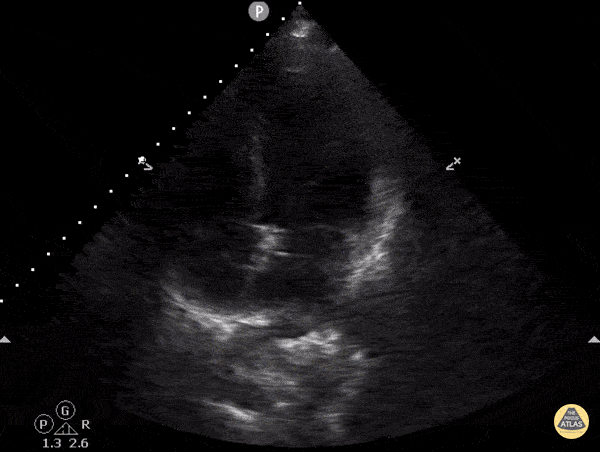

Left Ventricular Dysfunction - Reverse Takotsubo Cardiomyopathy

A 52-year-old female presented to the ED with acute onset of upper abdominal pain and cough productive of frothy, pink sputum. She was ill-appearing, tachypneic, tachycardic, and hypotensive. POCUS revealed severe hypokinesis of the LV basal wall with a hyperdynamic apex, and diffuse B lines in both hemithoraces. She was in cardiogenic shock secondary to basal (aka reverse) Takotsubo cardiomyopathy (TCM). This variant accounts for only ~3% of TCM cases. Interestingly, 6 months ago she suffered from the typical (apical) variant. The recurrence rate in the 1st year is ~1.5%, but having a different variant is even more rare! (The U/S clip has been slowed down to make it easier to visualize the RMWAs.) Dr. Sam Cochran